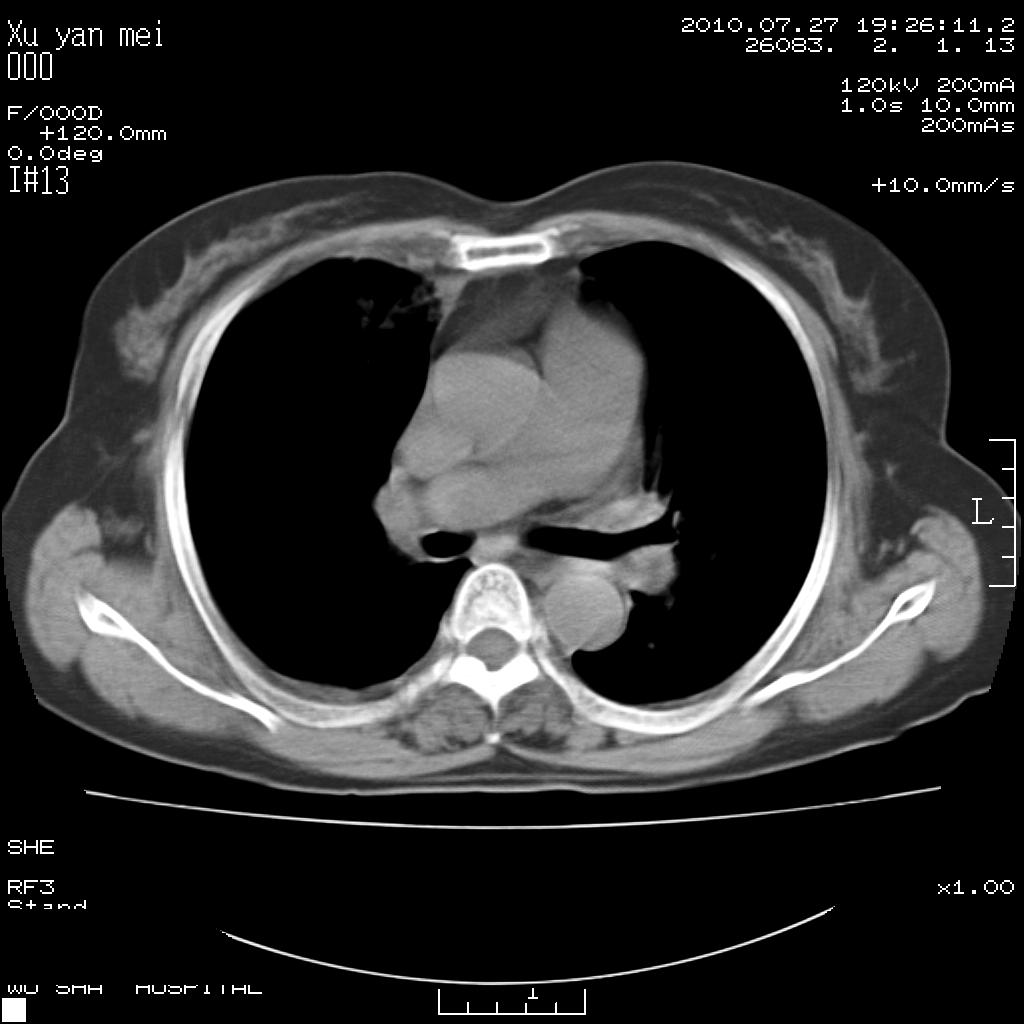

女,60岁,胸痛就诊,右肺结核?炎症?其它?(胸片右侧中上肺野确实看不到什么啊)

1)考虑两肺感染性病变;建议抗炎治疗后复查。2)双侧少量胸腔积液。

1)考虑两肺感染性病变;建议抗炎治疗后复查。2)右侧少量胸腔积液。

双肺炎症可能性大,建议抗炎后复查。右侧胸腔少量积液。双侧胸膜轻度增厚。

考虑两肺感染性病变;不除外肺栓;建议抗炎治疗后复查。